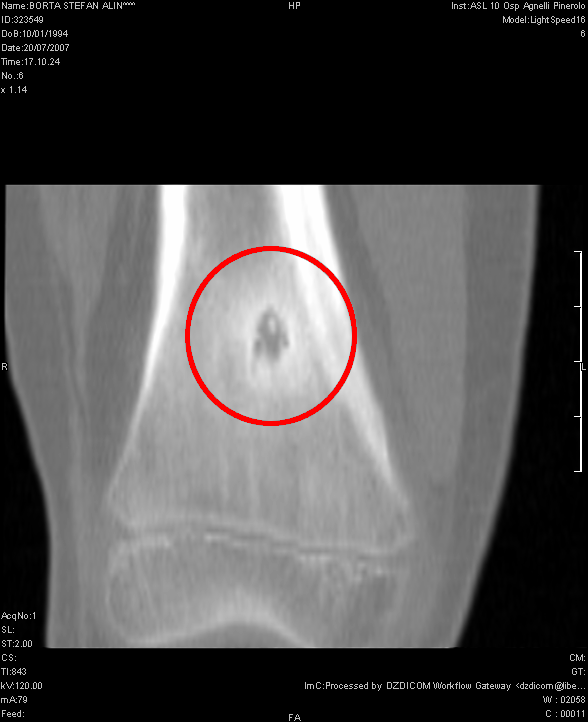

Osteoma osteoide

- Descrizione: Piccolo Tumore benigno che compare nell'Osso spongioso, principalmente in Gambe, Braccia e vertebre. È doloroso.